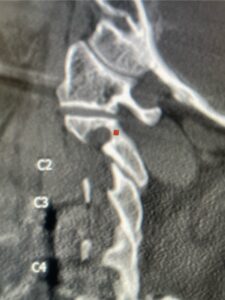

This 62 year-old female who had a prior ACDF from C3-C7 by an outside surgeon in 2009 and subsequent C5-C7 posterior cervical decompression and fusion in 2015 by our team, presents with progressive numbness, pain, and weakness of her arms. Above her prior anterior fusion, she had next segment degeneration with spinal stenosis resulting in spinal cord compression at C2-3 (Fig. 1).

Patient had an existing peripheral occipital nerve stimulator and therefore we had ordered a myelogram since it was not MRI compatible. The patient underwent a decompressive laminectomy and in situ fusion at C2-3. Care was made to preserve a good portion of the C2-3 facets bilaterally. It was felt that her C2 pars anatomically were not favorable to accept pars screws given the proximity of the vertebral foramen with a resultant narrow par (Fig. 2). She also had a normal C2-3 vertebral alignment. Post-operatively she had improvement of her arm pain and strength in right arm. In this case we made a decision to decompress the patient posteriorly given her prior anterior surgery, a more difficult approach to C23 disc space, and significant C23 disc collapse. A posterior approach was favorable in our opinion given the prior posterior surgery was more inferior with less scarring likely to be encountered in the C1-3 region. A posterior decompression also can yield a more adequate spinal cord decompression. Since we elected not to place pars screws because of her anatomy, and perform an in-situ fusion, careful attention was made to preserve as much of the C23 facet complex as possible.

Fig 2: Sagittal cervical CT pyelogram demonstrating a very narrow C 2 pars and prominent vertebral foramen making in unsafe to place a pars screw